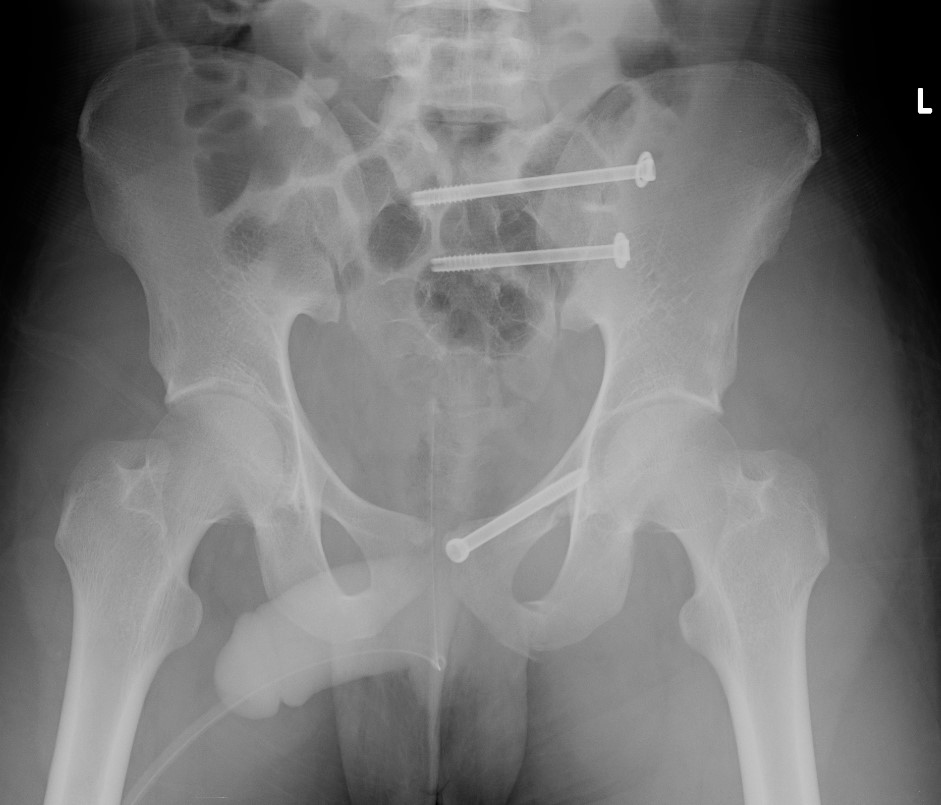

Percutaneous ramus screw

Vumedi pubic rami screw and IM nail

AO surgery reference pubic rami screw